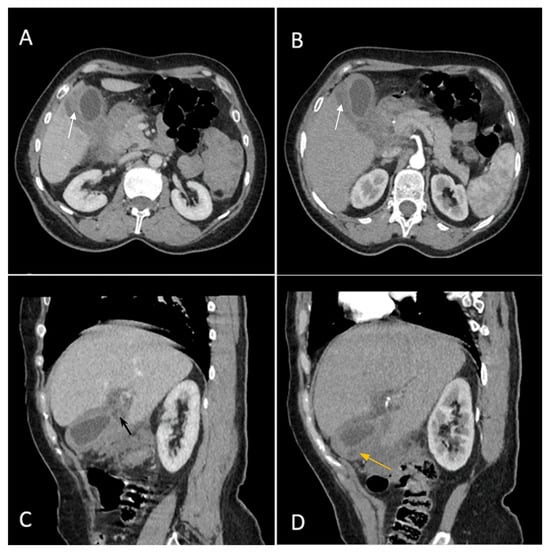

Biphasic (arterial phase followed by venous phase) contrast-enhanced emergency CT was performed (Figure 1), which clearly highlighted a gallbladder hydrops, with asymmetric, irregular gallbladder mural thickening, associated with multiple intraluminal mixed stones (Panel A). The tumoral mass extends directly into the adjacent liver parenchyma in segments IV and V and is in contact with the ascending colon (Panel C). Hepatomegaly can be observed (right hepatic lobe measures = 190 mm), with nodular lesions, disseminated in both hepatic lobes, hypodense, with rim peripheral contrast enhancement, more numerous in the right lobe, presenting various sizes (up to 35 mm in segment V) highly suggestive of liver metastases (Panel B and Panel C). Lymphatic metastases are common in gallbladder cancer. In this particular case, CT showed multiple lymph nodes enlargements in the hilar, mesenteric, celiac and precaval regions, up to 26/25 mm (measured in the hepatic hilum), with associated central necrosis (Panel D).

Figure 1. Multiplanar sections of contrast-enhanced CT acquisitions richly illustrating a low differentiated gallbladder adenocarcinoma. (A) Gallbladder hydrops (>40 mm transverse measurement, 142 mm longitudinal measurement) with asymmetric gallbladder mural thickening, 7 mm (white arrow), and multiple intraluminal mixed stones, 5–8 mm (black arrow). (B,C) Liver metastases—hypodense nodular hepatic lesions with rim contrast enhancement (yellow arrow). (C) Tumoral extension into IV, V segments of the right hepatic lobe and contact with the ascending colon (green arrow). (D) Lymphatic metastases (white stars).